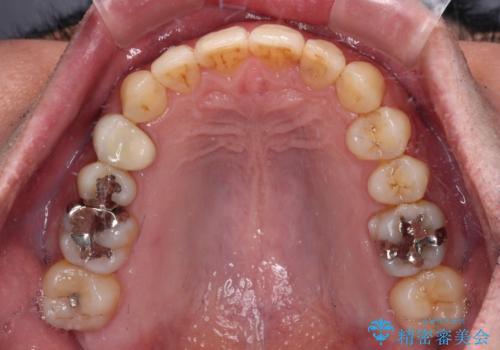

- 外に飛び出した側方の歯と、前歯のデコボコを気にして来院された患者様です。

IPR(歯と歯の間を削る)によってデコボコが解消するように設計し、インビザラインにより治療を行うこととしました。

治療途中で1年半以上通院されない時期があったため、後戻りが生じたことで治療期間が長くなってしまいました。

親知らずを抜去したことで、下顎のデコボコがきれいに解消されました。